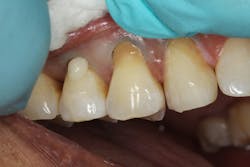

From the one- and one-and-a-half year postoperative images, we can analyze the longevity performance of the restorations. The restorations have proven to be color-stable and retain their polish and structural integrity (figures 5 and 6).References